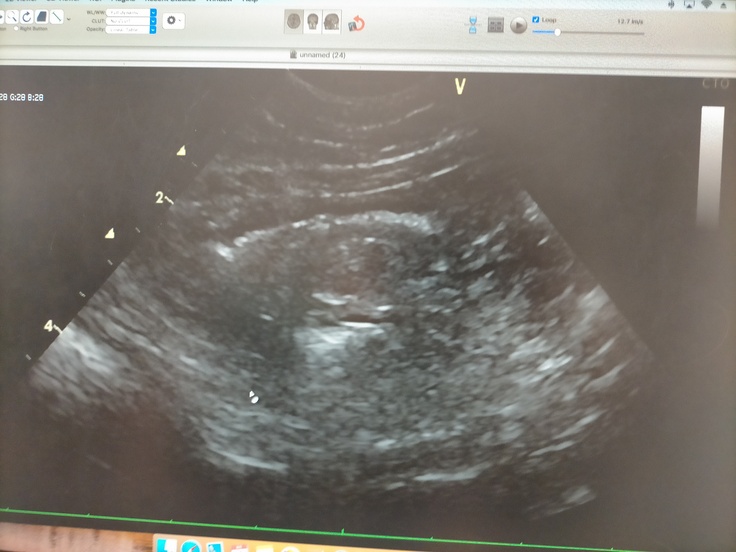

腸の中の腫れなし!内臓も綺麗!心配してた膀胱(前回脂肪と思われる白いモヤがあったり、おしっこの間隔が長い日があり)も問題なしで、

全身状態は非常に良く、再発の影もなしとのことで、遂に先生から

「寛解です!」